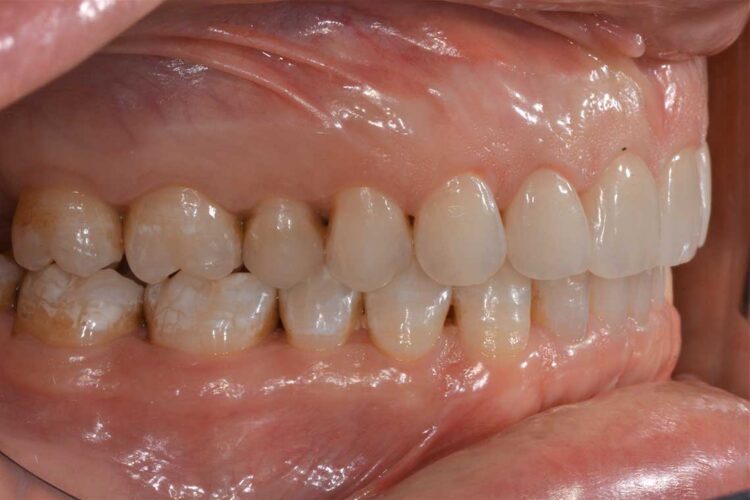

Ortodonzia allineatori – caso clinico 2